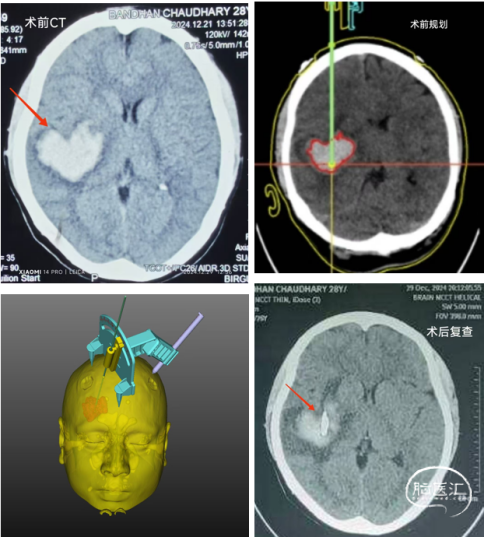

依次是術前CT的心形血腫,術前的平面規(guī)劃和手術設計,以及術后的CT復查,顯示引流管成為精準命中靶心的“丘比特之箭”

其它六七位醫(yī)生聚在我們這邊參觀。這邊的醫(yī)生大多在英國、美國、日本、中國及印度學習過,手術使用的無菌用品質量很好。唐醫(yī)生組裝好導向器和定向顱鉆,上臺不到20分鐘就完成了手術,看到黑紅色的血腫液被緩緩抽出,在場的醫(yī)護都面露笑容。好幾位醫(yī)生表示這樣簡便快捷又高度標準化的技術非常適合尼泊爾。

告別拉杰夫教授后我們去病房探望手術患者,患者完全清醒,感覺癱瘓十余天的左手力量有所恢復,頭痛也明顯減輕。可惜尼泊爾缺尿激酶,全城找到幾只鏈激酶我們又不敢用,要不然血腫清除會更迅速(感覺尼泊爾腦溢血治療的一些微創(chuàng)理念有待普及)。家屬非常高興,邀請我們一起合影。